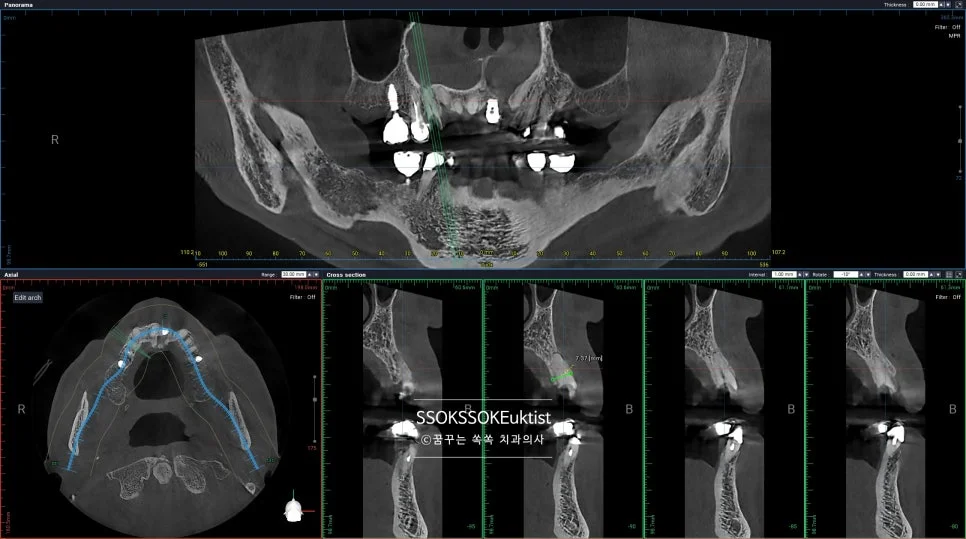

Step 2. CBCT 3차원 식립 계획

CBCT 3차원 사진을 기반으로 식립 위치 계획

3차원 사진(CT)를 기반으로 임플란트 식립 위치를 가늠하고 예쁘게 식립합니다!